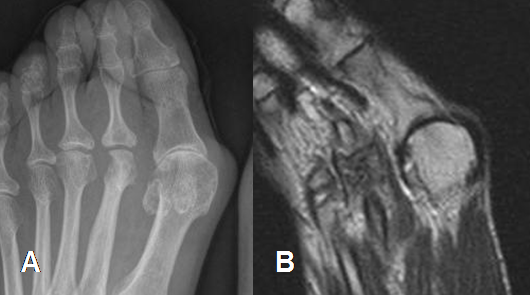

Fig 129. Artropatía degenerativa.

A: Rx AP y B: RM axial en T1. Cambios degenerativos en 1º articulación metatarsofalángica, con disminución del espacio articular y esclerosis.